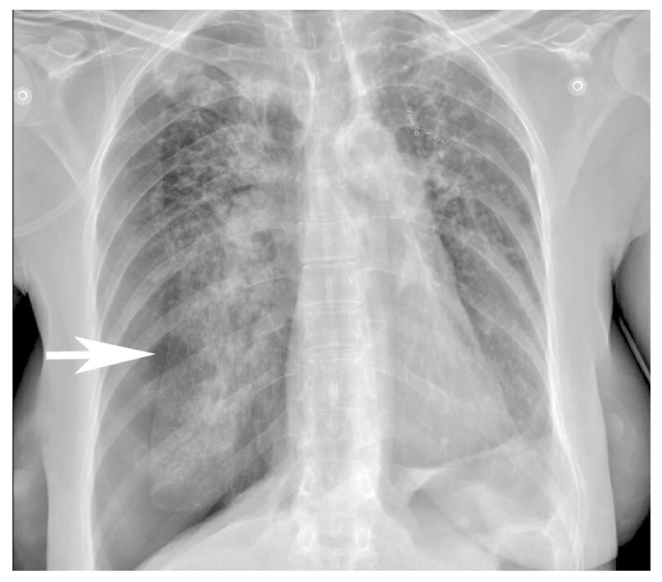

Результаты физикального, лабораторного и инструментального исследований. При первичном осмотре тахипноэ (частота дыхательных движений 39 в минуту), тахикардия (частота сердечных сокращений 115 в минуту), артериальное давление 110/70 мм рт.ст., насыщение крови кислородом (SpO2) 93%. Показатели общего и биохимического анализа крови в пределах референсных значений. При рентгенографии органов грудной клетки состояние после резекции I–II сегментов левого лёгкого, признаки массивного спонтанного пневмоторакса справа (рис. 3).

Рис. 3. Пациентка А., 53 года. Рентгенограмма грудной полости. Спонтанный пневмоторакс справа, коллабированное правое лёгкое (стрелка).

Лечение. Выполнена торакостомия с дренированием 1500 см3 воздуха. При контрольной компьютерной томографии определяются неполное расправление правого лёгкого, эмфизема мягких тканей грудной клетки (рис. 4, а). Пациентка хорошо перенесла процедуру, и симптомы патологического состояния уменьшились. На следующее утро у пациентки усилилась одышка, а сатурация кислорода (SpO2) снизилась до 86%. При повторной компьютерной томографии в левом лёгком определены множественные внутридольковые участки понижения прозрачности по типу матового стекла с гравитационными градиентами плотности (см. рис. 4, б). В совокупности с анамнезом данный симптом дал возможность прийти к заключению о развитии реэкспансивного отёка, так как у пациентки не было лихорадки и лейкоцитоза, характерных для пневмонии; отсутствовали признаки аспирации и перегрузки жидкостью, а также признаки почечной и сердечной недостаточности.

Рис. 4. Пациентка А., 53 года. Компьютерная томограмма грудной полости: а — скопление воздуха в правой плевральной полости (стрелка), эмфизема мягких тканей передней грудной стенки; б — скопление воздуха в правой плевральной полости (стрелка), эмфизема мягких тканей передней грудной стенки; снижение воздушности паренхимы левого лёгкого по типу матового стекла, обусловленное реэкспансивным отёком (головка стрелки).

Диагноз. Заключительный диагноз сформулирован следующим образом: «Реэкспансивный контралатеральный отёк левого лёгкого, вторичный по отношению к пневмотораксу правого лёгкого».

Исход и результаты последующего наблюдения. После соответствующей кислородотерапии, применения кортикостероидых препаратов и дренирования плевральной полости по Бюлау в течение 5 дней правое лёгкое удалось полностью расправить без развития ипсилатерального реэкспансивного отёка, а реэкспансивный отёк левого лёгкого полностью разрешился.